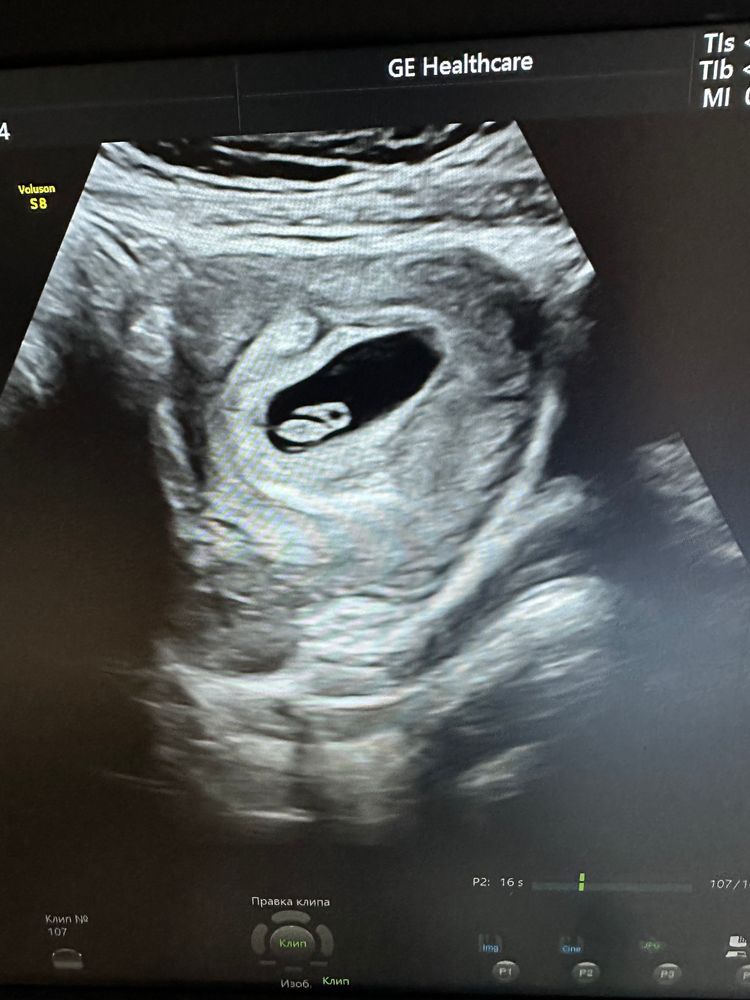

Птеродактель)) а у меня буратино походу))) Изображение А вообще, пол трудно разглядеть даже на 12 неделе. Остается только гадать и ждать второго скрининга)

Алёна К, а еще, судя по последнему фото, там птеродактель😂😂😂 смеюсь все утро с этого кадра😂😂😂

Екатерина, кстати похож🤣🤣🤣 цыпленочек🤣😂

Екатерина, и как мне теперь остановиться и не смеяться ааааа?🤣😂 разглядываю ваш снимок😂 чувствую себя маньяком 🤣🤣🤣🤣